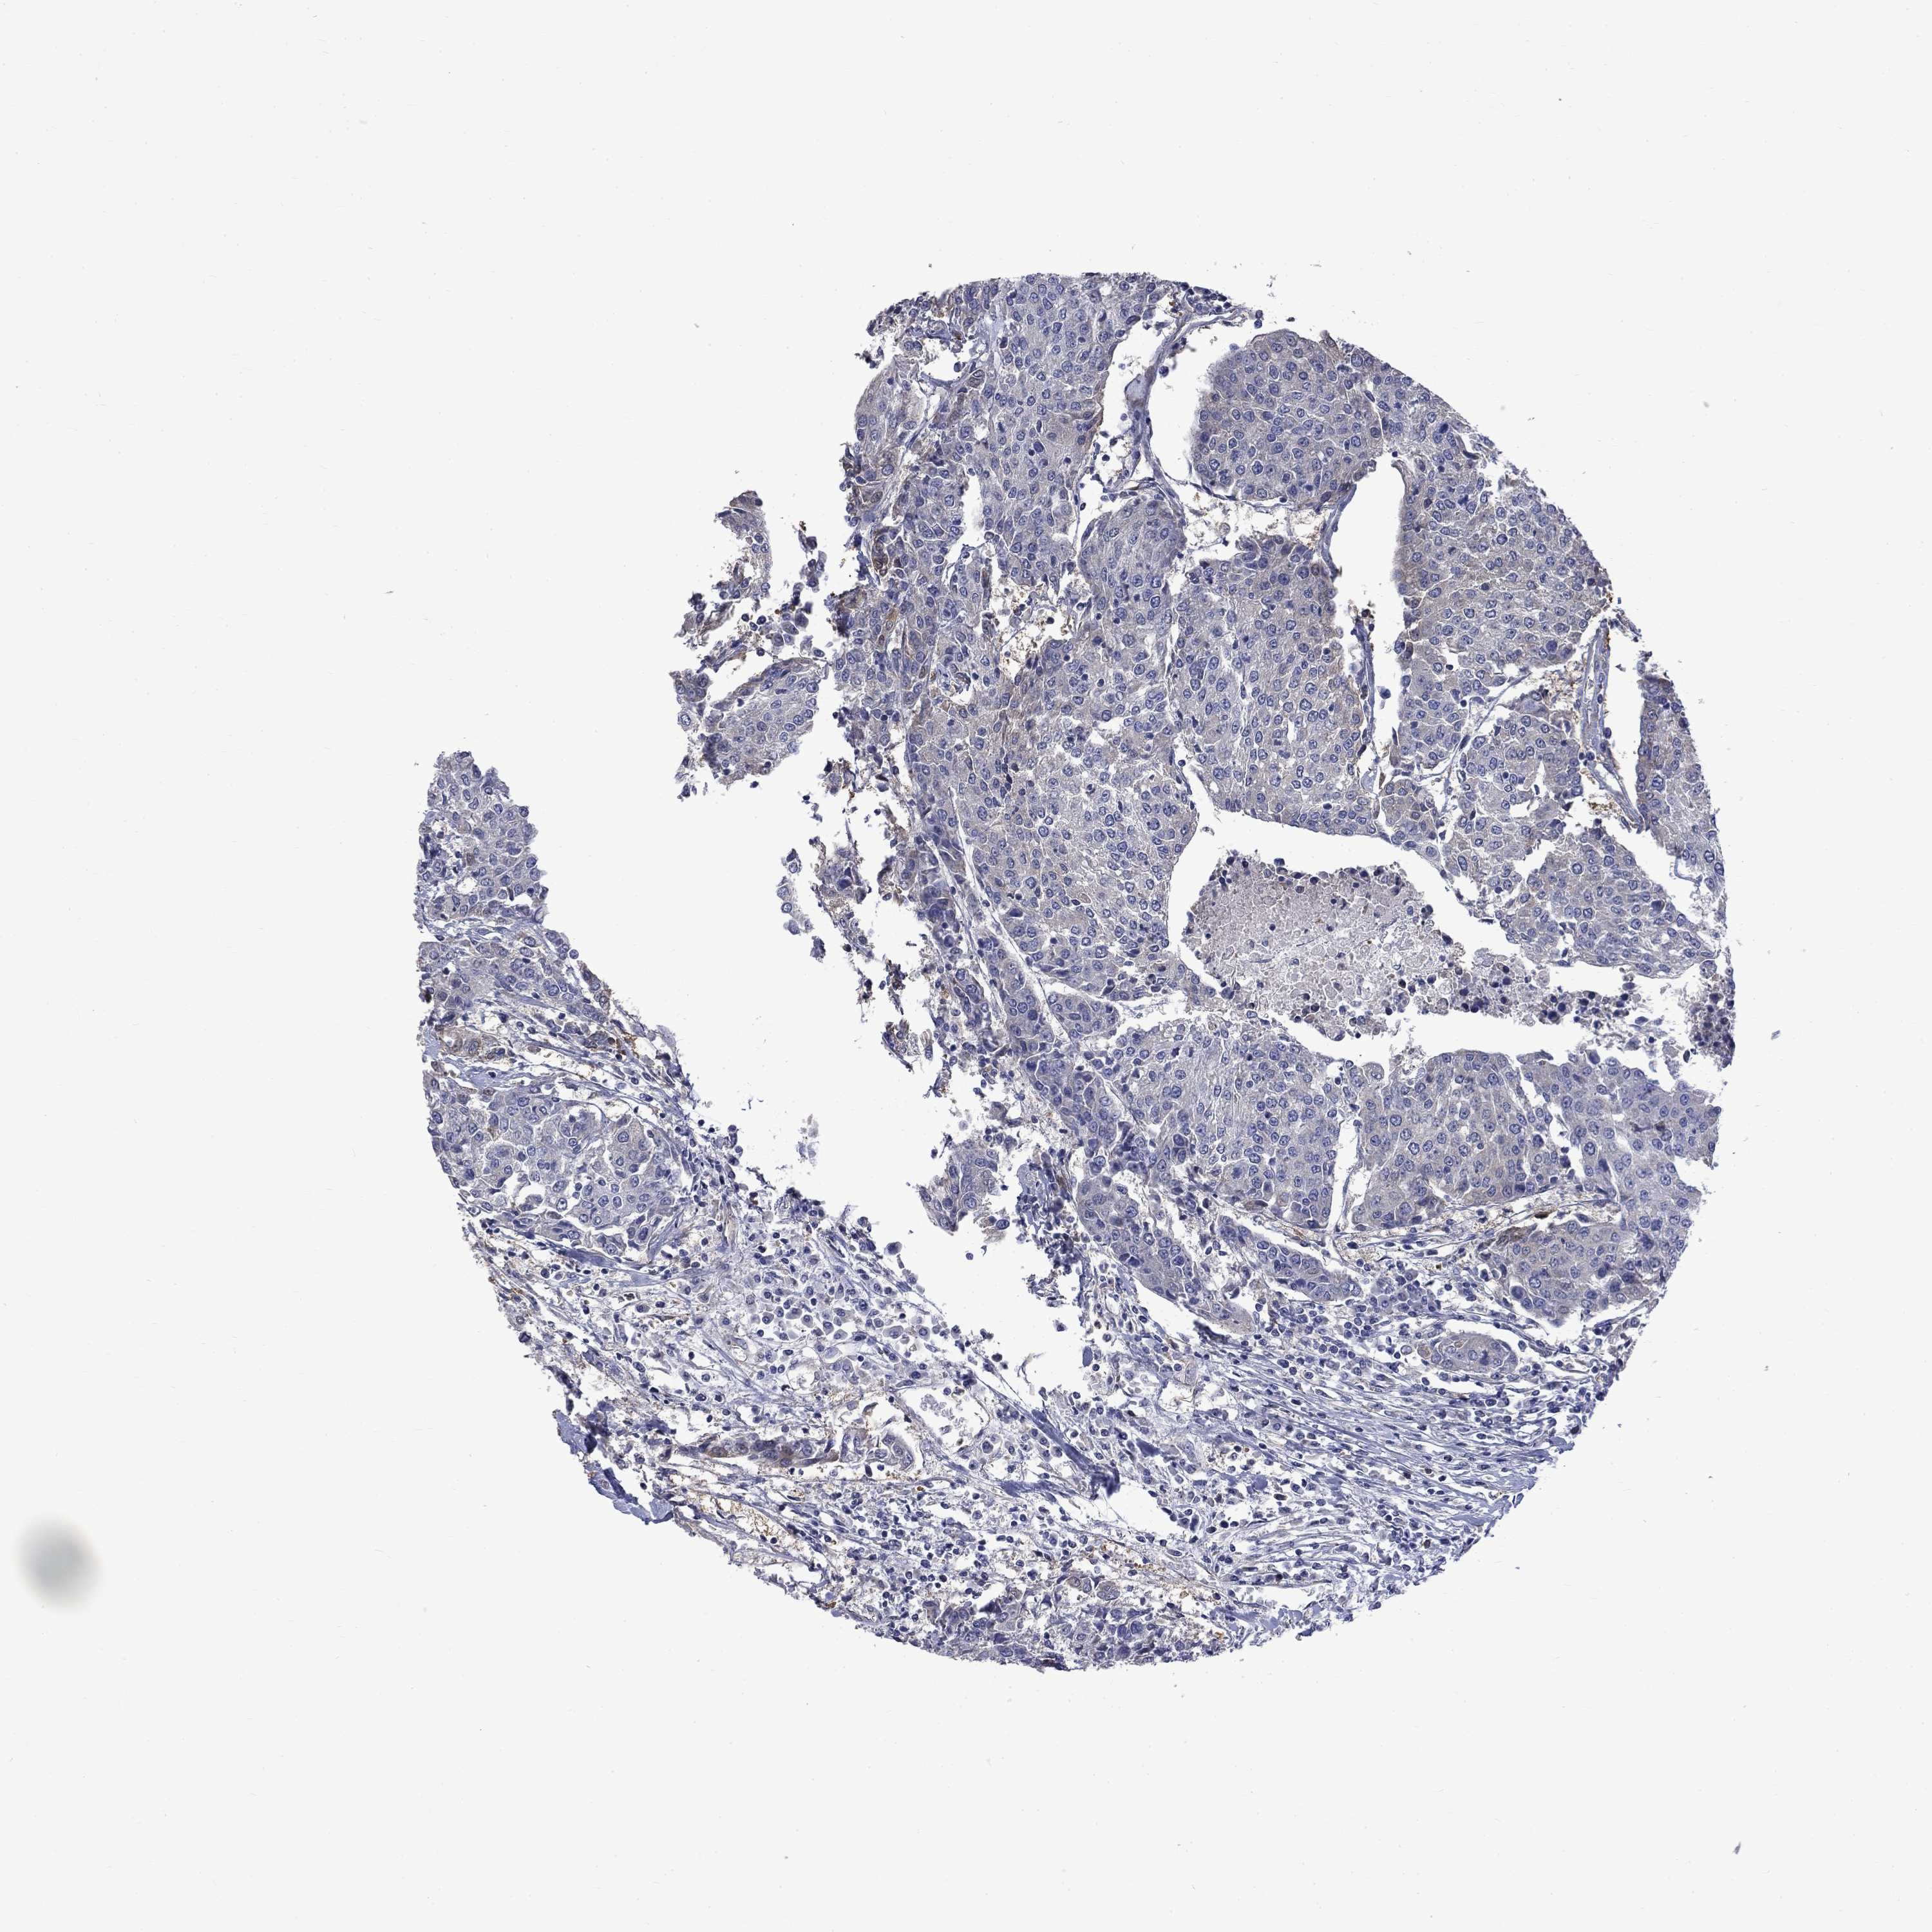

UROTHELIAL CANCER - Protein expressioni

A mouse-over function shows sample information and annotation data. Click on an image to view it in a full screen mode. Samples can be filtered based on level of antibody staining by selecting one or several of the following categories: high, medium, low and not detected. The assay and annotation is described here.

Note that samples used for immunohistochemistry by the Human Protein Atlas do not correspond to samples in the TCGA dataset.

Antibody stainingi

Antibody staining in the annotated cell types in the current human tissue is reported as not detected, low, medium, or high, based on conventional immunohistochemistry profiling in selected tissues. This score is based on the combination of the staining intensity and fraction of stained cells.

Each image is clickable and will lead to virtual microscopy that enables deeper exploration of all samples and also displays staining intensity scores, fraction scores and subcellular localization as well as patient and tissue information for each sample.

Antibody HPA017389

Antibody HPA063713

Staining

High

Medium

Low

Not detected

Intensity

Strong

Moderate

Weak

Negative

Quantity

>75%

75%-25%

<25%

None

Location

Nuclear

Cytoplasmic/membranous

Cytoplasmic/membranous,nuclear

Urothelial carcinoma, Low grade

Urothelial carcinoma, High grade

Urothelial carcinoma, NOS